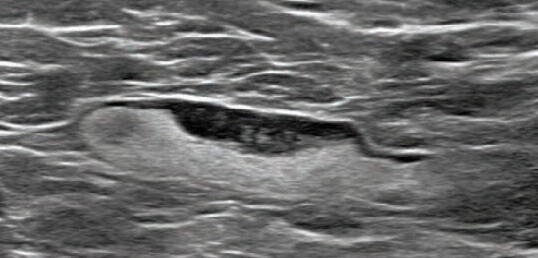

"So what happens is, if they come for a screening mammogram and they do see lymph nodes that are enlarged, then we will call them back from that screening mammogram more than likely for an ultrasound," Leverett said.